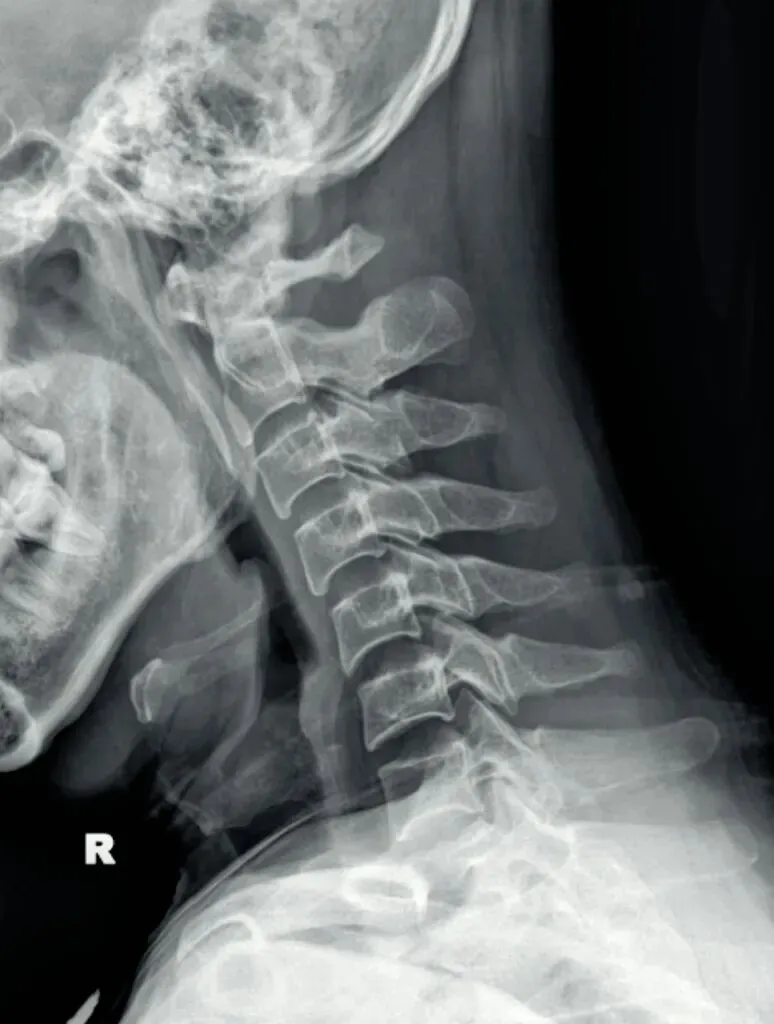

一骨是是我们主要在颈椎侧位X线片中观察椎体的形态与结构,查看椎体是否规则,

椎体边缘有无变尖或呈唇样改变的骨质增生。

椎体骨质有无破坏,密度是否正常,如肿瘤或者感染。

椎体的高度是否均匀,有无压缩变形。椎体高度减小可能提示骨质疏松、压缩性骨折

或椎体的发育异常等。

二弓指的是颈椎生理曲度,在颈椎侧位X线片中,正常生理状态下呈现向前凸出的弧形曲线,呈半C型前凸类似弓形,是人体脊柱生理曲度的重要组成部分。颈椎曲度变化能够反映颈椎整体功能的变化。

常见的颈椎曲度改变有曲度变直和曲度反曲。

颈椎生理曲度测量的方法多种多样,其中应用最广泛的测量方法是Borden法。从齿状突后上缘开始向下将每个椎体后缘相连成为一条弧线,然后从齿状突后上缘至C7椎体后下缘作一直线测量,两条线间最宽处的垂直横交线的距离即为颈椎生理曲度深度。

正常时,最宽处在C4椎体水平正常为12毫米,正负5毫米,小于7毫米为生理曲度变直,大于17毫米为生理曲度过度前屈,小于零时为生理曲度反曲。